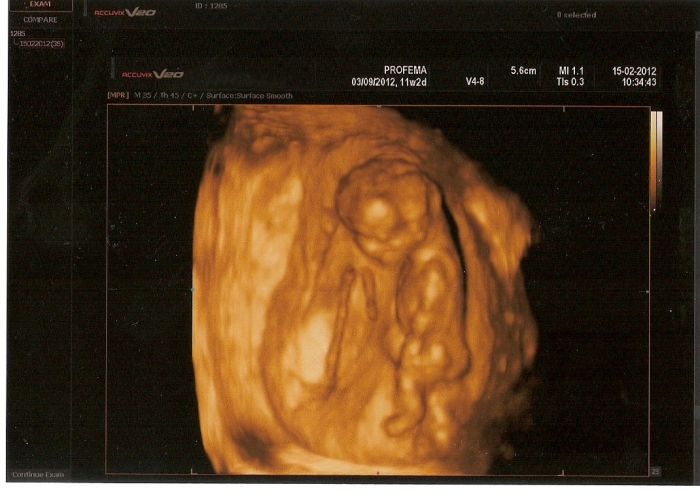

Jinak holčiny, ten podrobný screening mi dopadl dobře! Mám hroznou radost! Mimísek prospívá, Downův syndrom tam prý na 99ˇ% není, rozštěpy také ne, srdíčko se zdá v pořádku (ale ještě se vyvíjí, proto ještě bude další screening ve 20 týdnu). Viděla jsem mimíska, jak se mrská, bylo to moc příjemné. Celkový závěr: přestože mi je 40 let, nevidí důvod jít na odběry plodové vody, hurá hurá hurá!!!! Vím, že vyhráno ještě není, ale momentálně zatím lepší zprávy být nemohly! Hodím vám sem fotečku!

Miminka ( holčička ) je nádherná !!

jůůůůů!!!!!jsem kukla na fotečku a mám husí kůži!!!!!!to už je tak krásně vidět????krásný!!!!!!!!!!!!!!!!!!